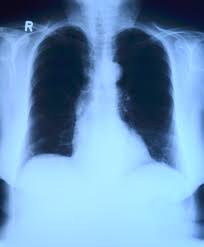

4) 진단 과정

CT, PET-CT, 조직검사 등을 통해 결절의 성격을 확인합니다. 영상 검사는 형태를 파악하는 데 유용합니다. 조직검사는 확진에 필요합니다. 환자의 연령, 흡연력도 진단에 중요한 요소입니다. 종합적으로 판단해야 합니다.